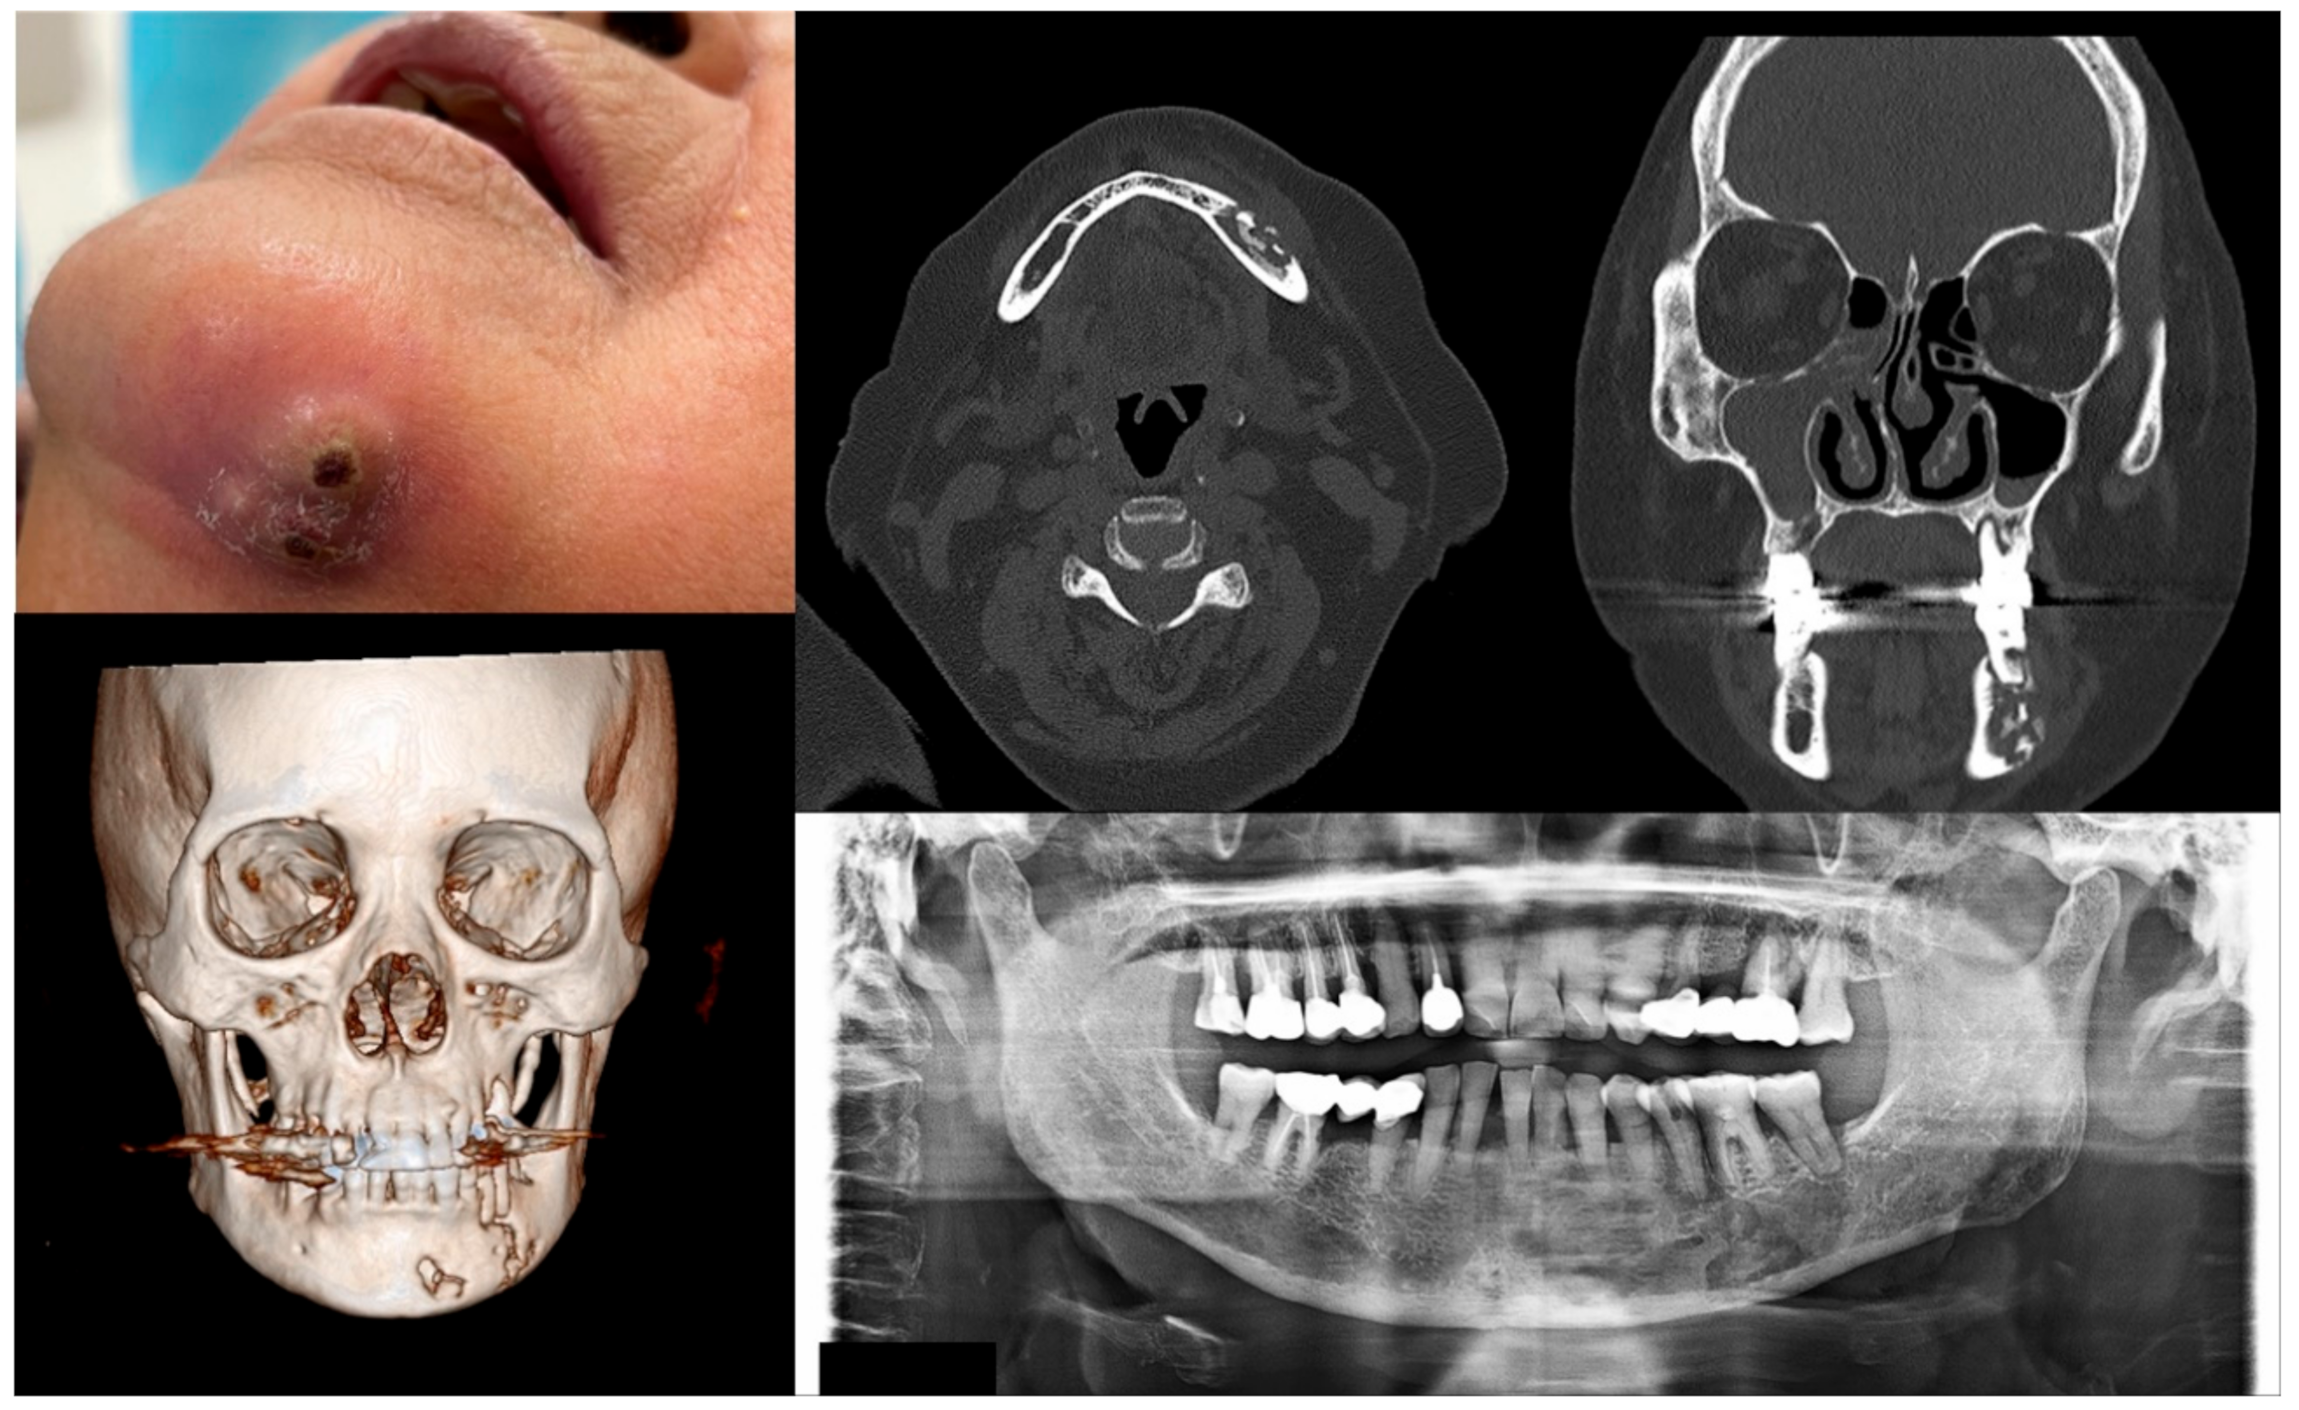

Figure 4.

Case 4 with MRONJ Stage 3: Clinical photo, panoramic view, and computed tomography imaging including three-dimensional reconstruction showing extraoral fistula and necrotic bone on the mandibular left anteroposterior area. An 80-year-old female patient with a history of intravenous administration of ibandronate and denosumab for one year was presented with inflammation and skin fistula on the chin area. She had undergone periodontal treatment on the left lower posterior teeth three months ago due to a periodontal abscess, but she was referred for recurrence with facial swelling from a private dental clinic. Bony lesions involving the inferior border of the mandible and the presence of extraoral fistula were observed.